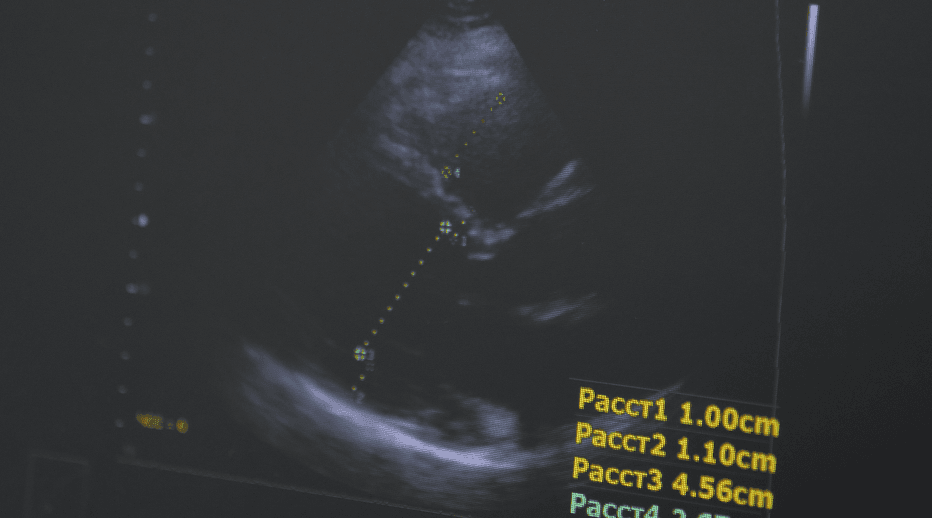

А ехо серця – це ультразвукове дослідження, яке показує його будову, анатомію, як рухаються клапани, чи немає якихось додаткових структур, запальних процесів тощо. Ми, по суті, бачимо будову серця в реальному часі.

Електрокардіографію, ехокардіографію (УЗД серця). Проводимо лабораторні дослідження, такі як ліпідограма, коагулограма, і весь спектр кардіологічних обстежень. Також у нас є сучасні методи діагностики: МРТ, КТ, коронарографія – обстеження серця та судин на наявність бляшок – атеросклеротичних або інших утворень. Це допомагає в діагностиці та запобіганні таким явищам, як ішемічна хвороба серця, інфаркт міокарда.